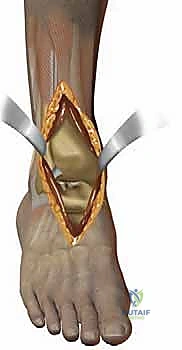

لفهم أهمية وتعقيد جراحة استبدال مفصل الكاحل، يجب أولاً أن نفهم كيف يعمل هذا المفصل الطبيعي المذهل. الكاحل ليس مجرد مفصل مفصلي بسيط (Hinge Joint) يتحرك لأعلى ولأسفل فقط، بل هو هيكل ديناميكي معقد يتحمل ضغوطاً هائلة تفوق وزن الجسم بعدة أضعاف أثناء المشي والجري.

يتكون مفصل الكاحل الأساسي (المفصل الظنبوبي الكاحلي - Tibiotalar joint) من التقاء ثلاث عظام رئيسية:

1. عظمة الظنبوب (Tibia): وهي عظمة الساق الكبرى، وتشكل السقف والجزء الداخلي من الكاحل (الكعب الداخلي - Medial Malleolus).

2. عظمة الشظية (Fibula): وهي عظمة الساق الصغرى، وتشكل الجزء الخارجي من الكاحل (الكعب الخارجي - Lateral Malleolus).

3. عظمة الكاحل (Talus): وهي العظمة السفلية التي تستقر داخل التجويف الذي تشكله عظمتا الساق، وتعمل كنقطة ارتكاز محورية للقدم.

تُغطى نهايات هذه العظام بطبقة ناعمة ومرنة تسمى "الغضروف المفصلي" (Articular Cartilage). هذا الغضروف يعمل كوسادة ممتصة للصدمات ويسمح للعظام بالانزلاق فوق بعضها البعض باحتكاك يكاد يكون معدوماً. علاوة على ذلك، يُفرز المفصل سائلاً زلالياً (Synovial Fluid) يعمل كزيت تشحيم لضمان نعومة الحركة. عندما يتضرر هذا الغضروف لأي سبب، تبدأ العظام بالاحتكاك المباشر، مما يسبب الألم الشديد، التورم، وفقدان القدرة على الحركة؛ وهنا تبرز الحاجة الماسة للتدخل الطبي.

1. نظام سالتو لمفصل الكاحل الكلي (Salto Total Ankle Prosthesis - Mobile Bearing)

مفصل سالتو الأصلي هو ثمرة أبحاث أوروبية مكثفة. تم تطويره بين عامي 1994 و 1996، وبدأ استخدامه السريري بنجاح باهر في يناير 1997.

* التصميم الميكانيكي: يُعرف بأنه نظام ذو "مكون متحرك" (Mobile-bearing). يتكون من ثلاثة أجزاء رئيسية:

1. مكون معدني يثبت في أسفل عظمة الساق (Tibia).

2. مكون معدني يثبت في أعلى عظمة الكاحل (Talus).

3. قطعة بلاستيكية من البولي إيثيلين عالي الكثافة (Polyethylene insert): هذه القطعة ليست ثابتة، بل تنزلق بحرية بين المكونين المعدنيين.

* الميزة الكبرى: هذا التصميم يسمح بـ "التموضع الذاتي" (Self-alignment). أثناء الحركة، تتحرك القطعة البلاستيكية لتتكيف مع القوى الميكانيكية، مما يقلل من الضغط الواقع على واجهة التثبيت بين المعدن والعظم، ويحاكي حركة الكاحل المعقدة بشكل رائع.

* التثبيت: هو مفصل "غير إسمنتي". يتم تغطية الأسطح المعدنية الملامسة للعظم بطبقة مسامية من التيتانيوم وهيدروكسي أباتيت (Hydroxyapatite). هذه الطبقة تشجع العظم الطبيعي للمريض على النمو داخل مسام المفصل (Bone Ingrowth)، مما يوفر تثبيتاً بيولوجياً صلباً يدوم لسنوات طويلة.